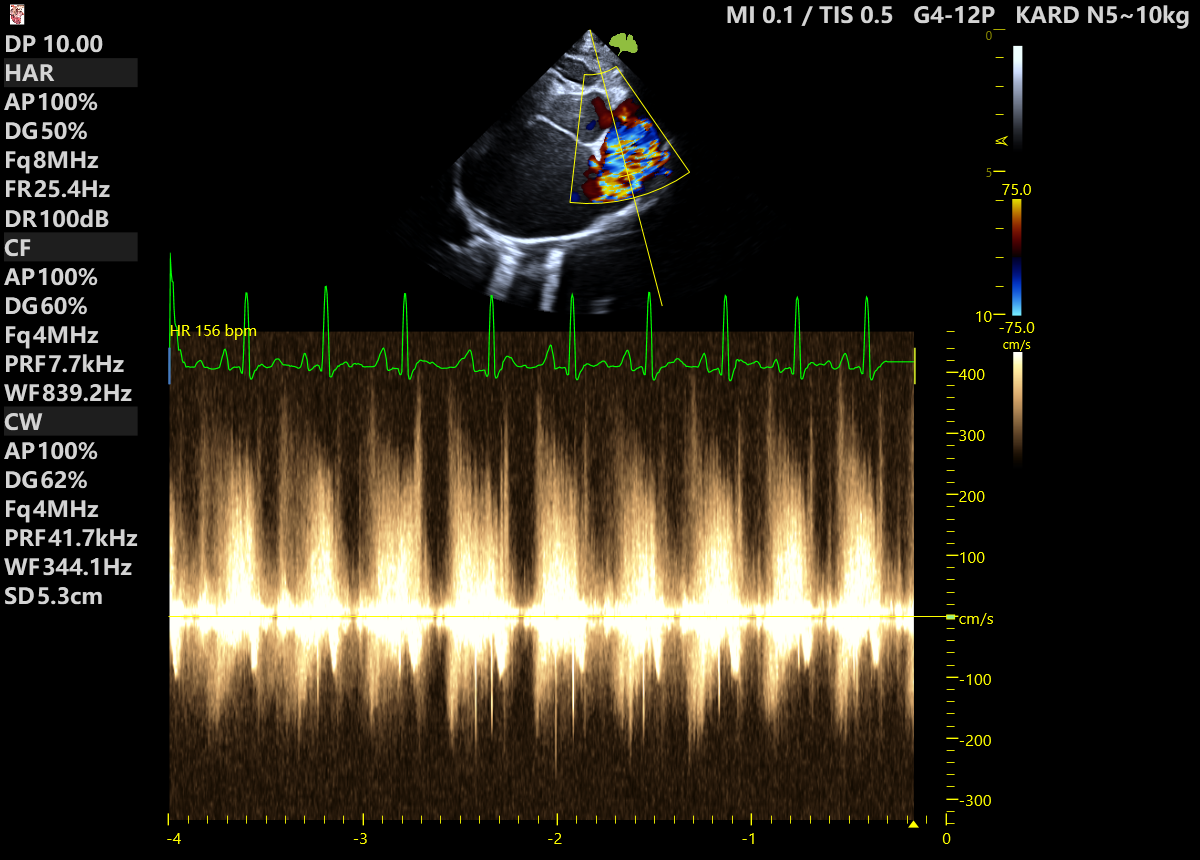

Badanie USG przeprowadziła lek.wet. Monika Morawska z MOONVET Aparat: VINNO G65VET Pacjent: 9-letnia, kastrowana kotka, u której wcześniej wykonano amputację kończyny miednicznej z powodu rozrostu w okolicy stawu skokowego. Histopatologia guza wskazała na mięsaka —złośliwy nowotwór pochodzenia mezenchymalnego. Podczas badania stwierdzono powiększenie prawego węzła chłonnego biodrowego pośrodkowego oraz węzła pachwinowego. Pobrany materiał z węzła biodrowego […]